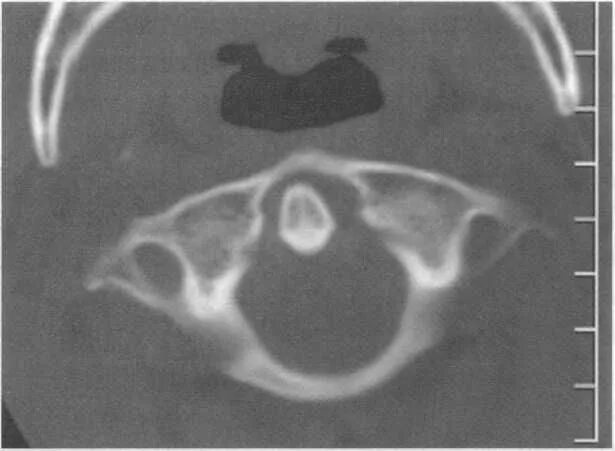

Атлант кт